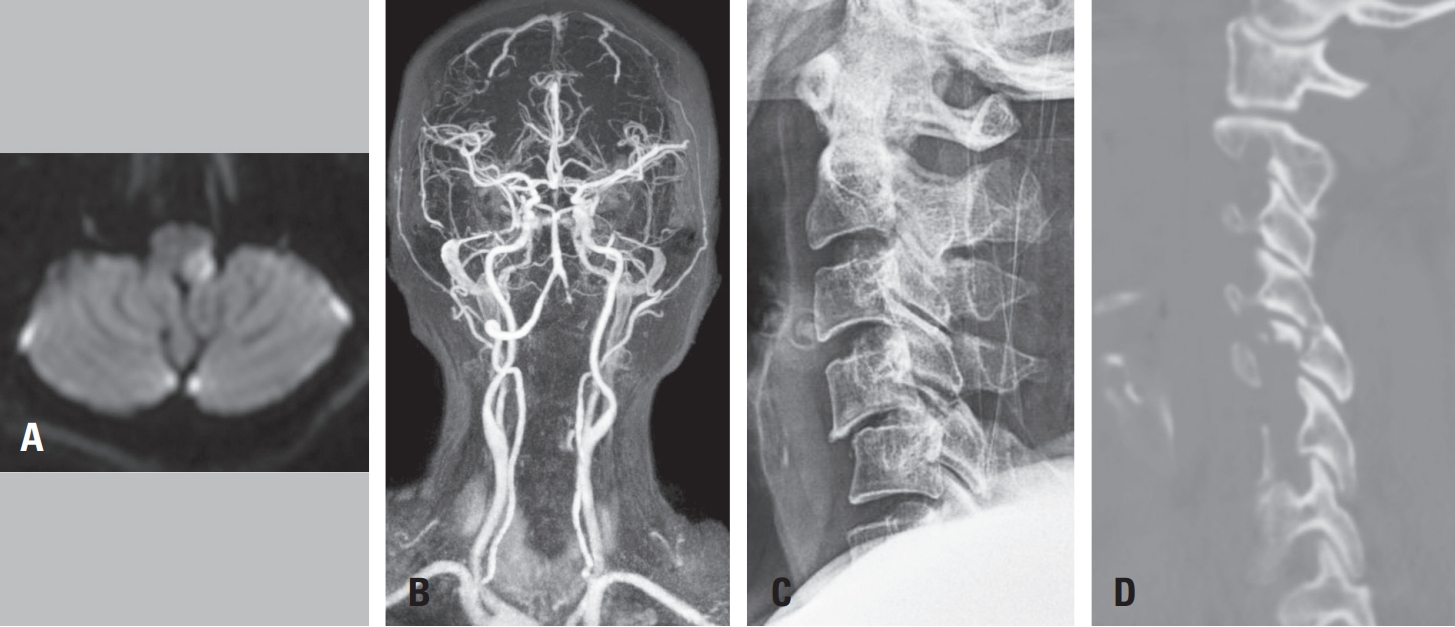

Postoperatively, her upper limb strength improved to 4/5 bilaterally, and sensory deficits resolved. Twelve hours after surgery, she developed new left facial numbness. Repeat neurologic examination showed right arm strength of 4/5 and near-intact strength on the left. Given the known vertebral artery occlusion, an urgent brain MRI was obtained; diffusion-weighted imaging revealed a high-signal lesion in the left lateral medulla (

Fig. 3A), and MR angiography demonstrated dissection-related occlusion of the left vertebral artery (

Fig. 3B). Aspirin therapy was initiated in consultation with the neurovascular team.

Fig. 3.

(A) Diffusion-weighted MRI showing acute infarction in the left lateral medulla. (B) MR angiography confirming occlusion of the left vertebral artery.